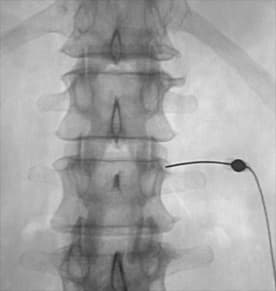

Пацієнту, який лежить на животі під місцевою анестезією виконується прокол шкіри голкою, яка встановлюється під рентген – контролем або КТ – контролем, прямо до суглоба, через просвіт голки до суглоба підводиться лазерний світловод. При включенні лазера на кінці світловода створюється висока температура, яка і руйнує фасеточний нерв. Процедура триває від 15 до 25 хвилин, після якої пацієнт відразу відчуває зменшення болю.